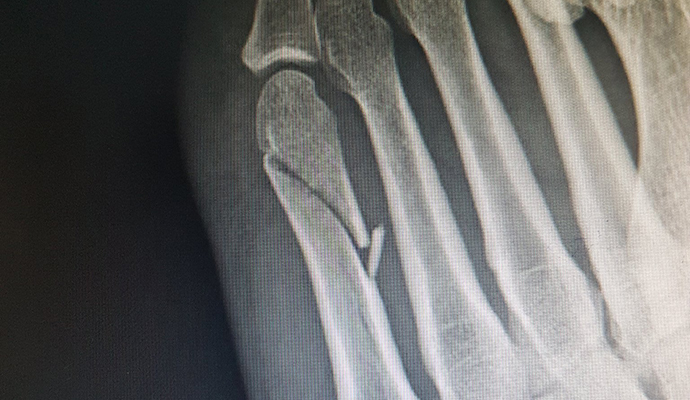

Así quedó el pie de Fernando Alarza tras completar medio triatlón con una fractura

Las pruebas, en concreto una radiografía, acabaron confirmando lo que Alarza se temía. Sufre una rotura del quinto metatarsiano de su pie izquierdo y deberá estar de baja hasta que se solvente. De este modo, prácticamente da por terminada la temporada.